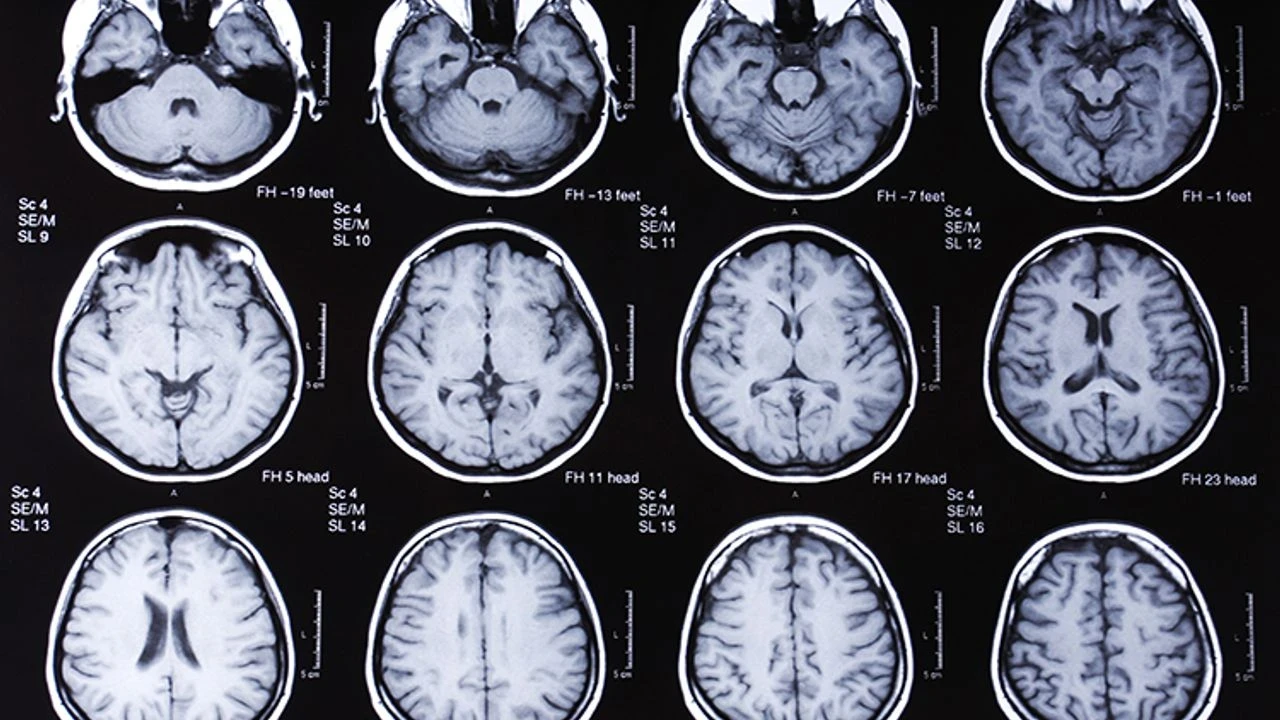

Prion hastalığı, merkezi sinir sistemini etkileyen, ilerleyici ve ölümcül seyreden nörodejeneratif bir rahatsızlıktır. Bu hastalığa, “prion” adı verilen anormal yapıya sahip proteinler neden olur. Normalde zararsız olan bu proteinler, yapılarındaki bozulma nedeniyle diğer sağlıklı proteinleri de etkileyerek sinir hücrelerinde tahribata yol açar.

Prion Hastalıkları ve Bulaş Yolları

Prion hastalıkları, genel olarak beyinde süngerimsi dejenerasyona neden olur. İnsanlarda görülen en bilinen prion hastalığı türü Creutzfeldt-Jakob Hastalığı (CJD)’dır. Hayvanlarda ise “Deli Dana Hastalığı” (BSE - Bovine Spongiform Encephalopathy) bu grubun en yaygın örneklerindendir.

Prion hastalıkları genellikle sinsice başlar ve ilerleyicidir. Hafıza kaybı, kişilik değişiklikleri, denge ve koordinasyon bozuklukları, konuşma bozuklukları, görme problemleri, kas kasılmaları ve istemsiz hareketler, ileri evrede bilinç kaybı ve koma gibi belirtiler görülebilir. Bu belirtiler kesin tanı için nörolojik değerlendirme ve özel testler gerektirir.